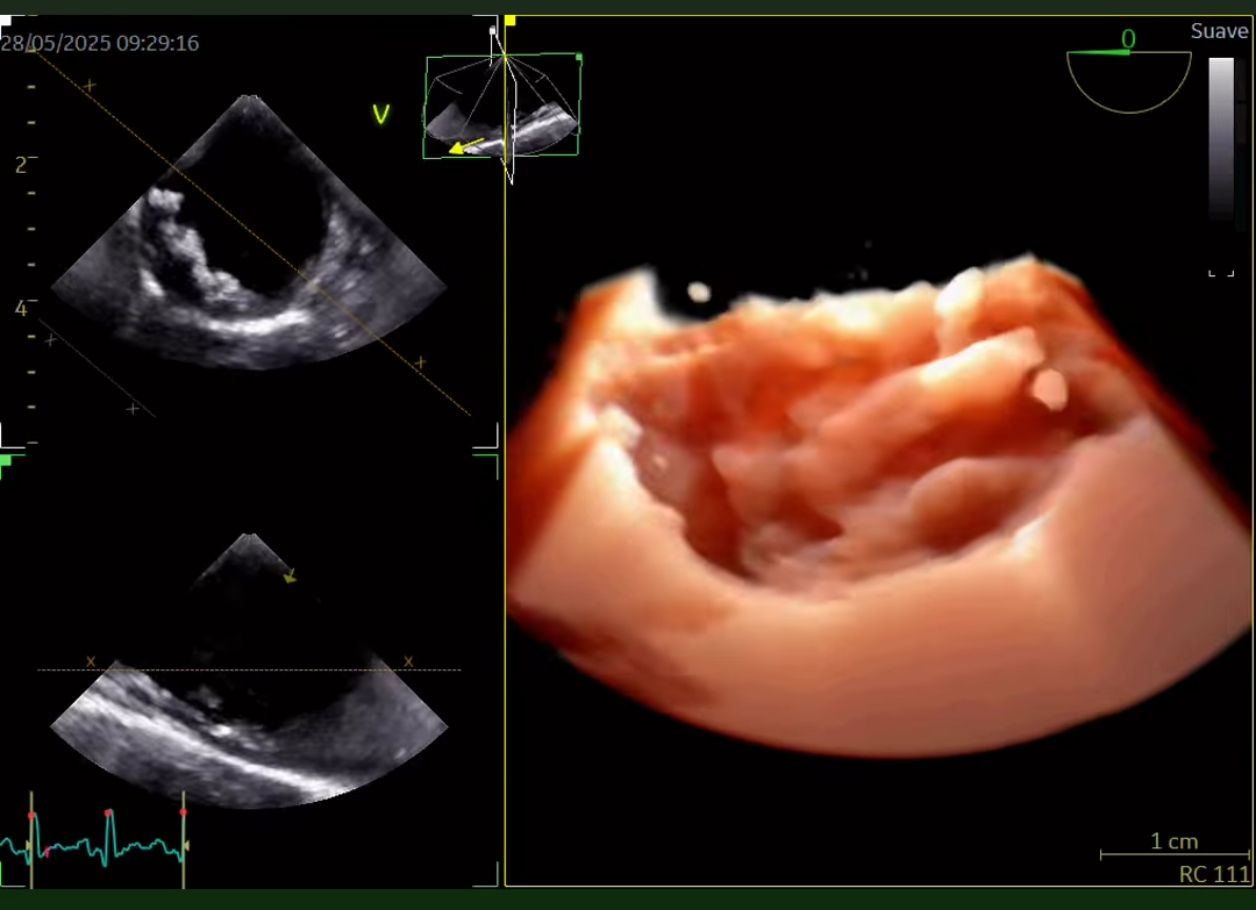

Soy el Dr. José Alberto Sánchez Toscano, con una subespecialidad en Cardiologia (2021-2023) y una alta especialidad en ecocardiografía transtoracico tridimensional en adultos (2024-2025). Egresado del Instituto Nacional de Cardiología "Ignacio Chávez" y certificado por el consejo mexicano de Cardiologia. Diplomado en Patología aórtica en la práctica clínica por la Universidad de Alcalá, Valencia 2023-2024).

Misión Profesional Como médico especialista en Cardiología y Ecocardiografía bidimensional y tridimensional, mi misión es brindar atención cardiovascular de alta precisión, combinando tecnología avanzada con un enfoque humano y personalizado. Me dedico a prevenir, diagnosticar y tratar enfermedades del corazón con excelencia médica, ayudando a cada paciente a comprender su salud cardiaca y tomar decisiones informadas. Busco generar confianza, bienestar y resultados concretos, promoviendo evaluaciones ecocardiográficas detalladas y confiables que pueden marcar la diferencia en el cuidado oportuno del corazón.

• Ecocardiografía